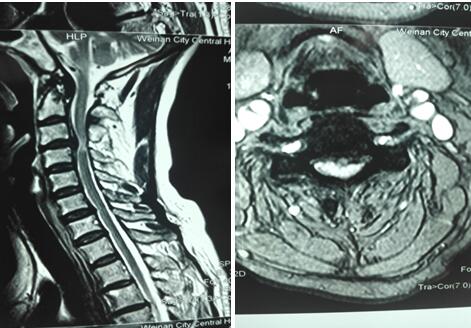

术前颈椎MR检查